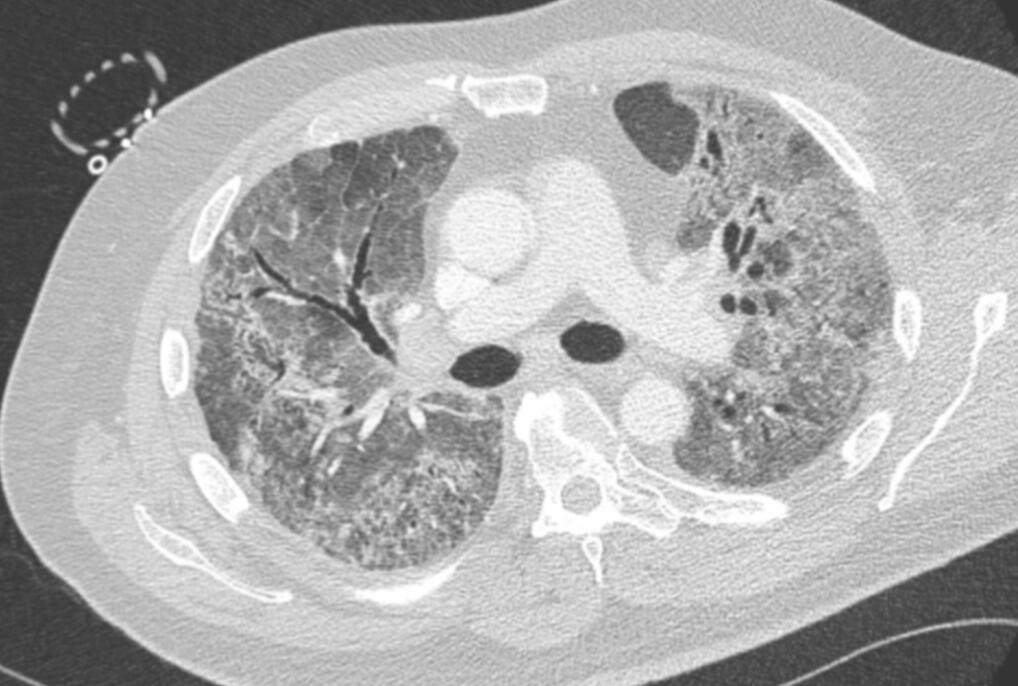

Lungs appearances after COVID-19 (High resolution CT scan)